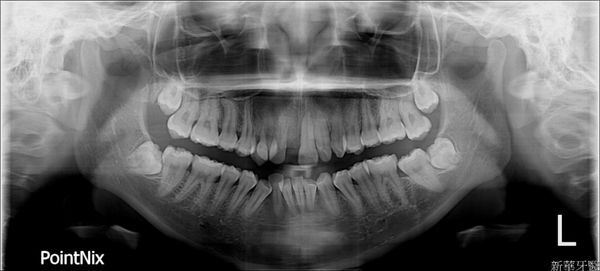

第一次初診文杰醫師先透過X片跟口內檢查約略幫我看了一下

眼前X光片裡可以看到左右兩顆強而有力的智齒正推擠前方臼齒,

在醫生詳細的介紹後才知道會有小暴牙是因為水平智齒推擠造成,